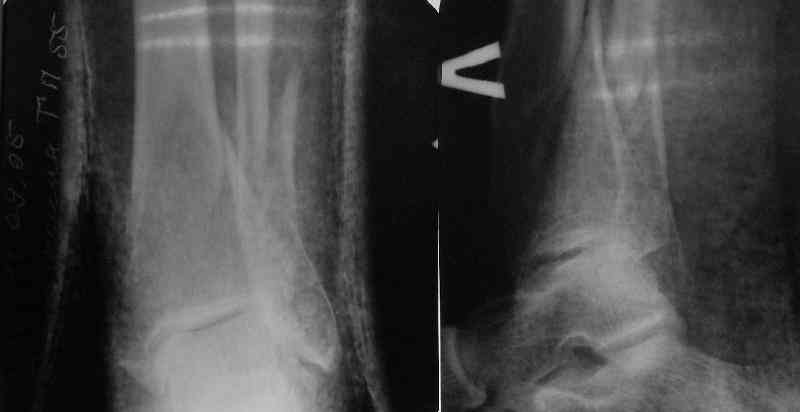

Very interesting application, but is the final position in a little distal varus with some fibula

distraction? Would that have been eliminated by fibula plating?

At least both the ankle mortise and tibial alignment look acceptable, don't they?

In delayed cases acute length restoration performed only in the tibia may leave the fibula shortened thus change the mortise. So it is reasonable to restore length of both bones simultaneously by distractor and fix the fibula not with open reduction and plating but just by a single perQ screw. Example attached.